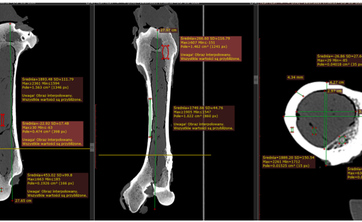

Korelacja własności mechanicznych kości zwierzęcych z pomiarami uzyskanymi w...

08-02-2023 r.

Dr Leszek Pyziak wygłosił referat nt. Korelacja wyników Ilościowej tomografii komputerowej (QCT) gęstości mineralnej kości zapisanych w skali Haunsfield